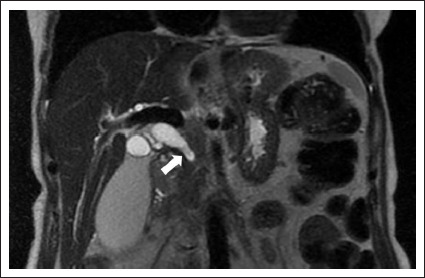

Materials and methods: This retrospective, single-center study was conducted between January 2022 and April 2023, involving a total of 16 patients. Of the patients, 10 were male (62.5%), and 6 were female (37.5%). The average age of the patients was 68.1±8. All patients underwent the procedure using an endobiliary biopsy brush under ultrasound and fluoroscopic guidance.

Results: Technical success was achieved in all patients (100%). Cell detection was not observed in biopsy samples from 2 patients (12.5%), resulting in a diagnostic success rate of 87.5%. Access was made to the right biliary system in 14 patients (87.5%) and to the left biliary system in 2 patients (12.5%). Biopsy locations included the common bile duct in 12 patients (75%), hepatic hilum in 2 patients (12.5%), and bilioenteric anastomosis line in 2 patients (12.5%). The mean fluoroscopy time was 16.2±7.1 minutes. The average radiation dose was 660±370 mSv. Pathological diagnosis revealed malignancy in 8 patients (50%) and benign findings in 6 patients (37.5%). Liver abscess requiring drainage developed in 2 patients (12.5%).

Abstract Image